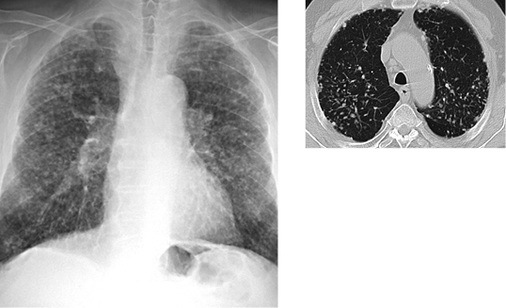

In der Thoraxaufnahme kommen im Gegensatz zu den klassischen Verlaufsformen mit nodulärem bzw. nodulär-retikulärem Bildmuster Milchglastrübungen zur Darstellung. Der Befund kann aufgrund der oft symmetrischen und bevorzugt perihilären Ausbreitung einem Lungenödem ähneln. Computertomographisch zeigen sich fokale Milchglastrübungen und Verdickungen der interlobulären Septen sowie des axialen Interstitiums, vereinbar mit einem Crazy-paving-Muster („crazy paving“ = Mosaikpflaster). Diese Befunde erinnern bildmorphologisch an eine primäre Alveolarproteinose (  Abb. 2 ). Im Gegensatz zur Alveolarproteinose finden sich jedoch zusätzlich unscharf begrenzte zentrilobuläre Verdichtungen und größere konfluierende Konsolidierungen (Alper et al. 2008; Doganay et al. 2010; Marchiori et al. 2007; Taeger 2011). Punktförmige Verkalkungen innerhalb der Konsolidierungen wurden von Marchiori et al. (2007) in 83 % der Fälle gesehen und als charakteristisch für eine Silikoproteinose beschrieben. Die Läsionen sind überwiegend dorsal angeordnet. In etwa 50 % der Fälle finden sich vergrößerte mediastinale Lymphknoten, die zum Teil auch verkalken (Marchiori et al. 2007), eierschalenartige Verkalkungen wurden jedoch nicht nachgewiesen. Uehlinger beschreibt erstmals 1949 bei starker Ausprägung der Erkrankung eine Betonung der Befunde in den Unterfeldern, diese wird auch in späteren Arbeiten bestätigt.